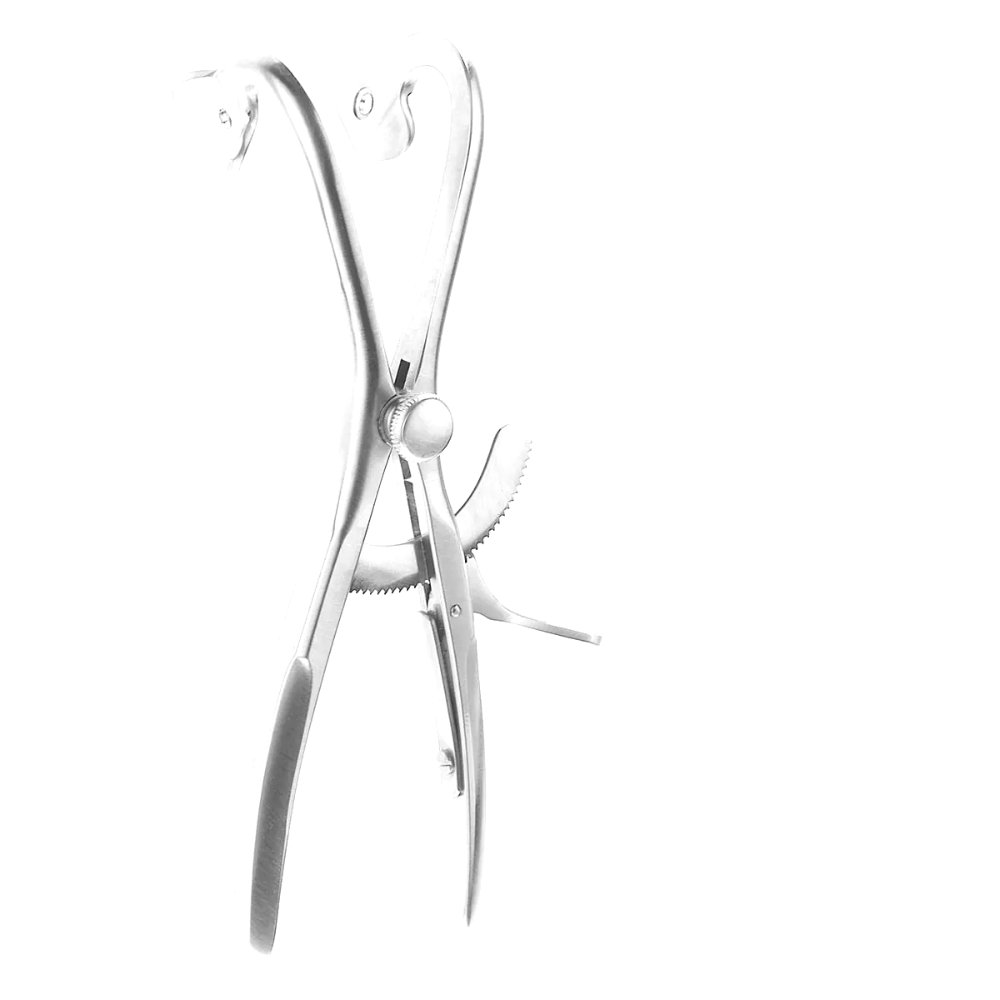

The ENT Denhardt Mouth Gag with Silicone Inserts 5 1/8″ is engineered to provide gentle retraction with maximum patient safety. The silicone-lined blades protect delicate oral tissues from pressure injury and slippage, making it ideal for pediatric and sensitive oral surgeries. The robust stainless-steel frame ensures stability, while the non-slip silicone padding offers added comfort and grip during procedures.

Size: 5 1/8″ with silicone-lined blades.